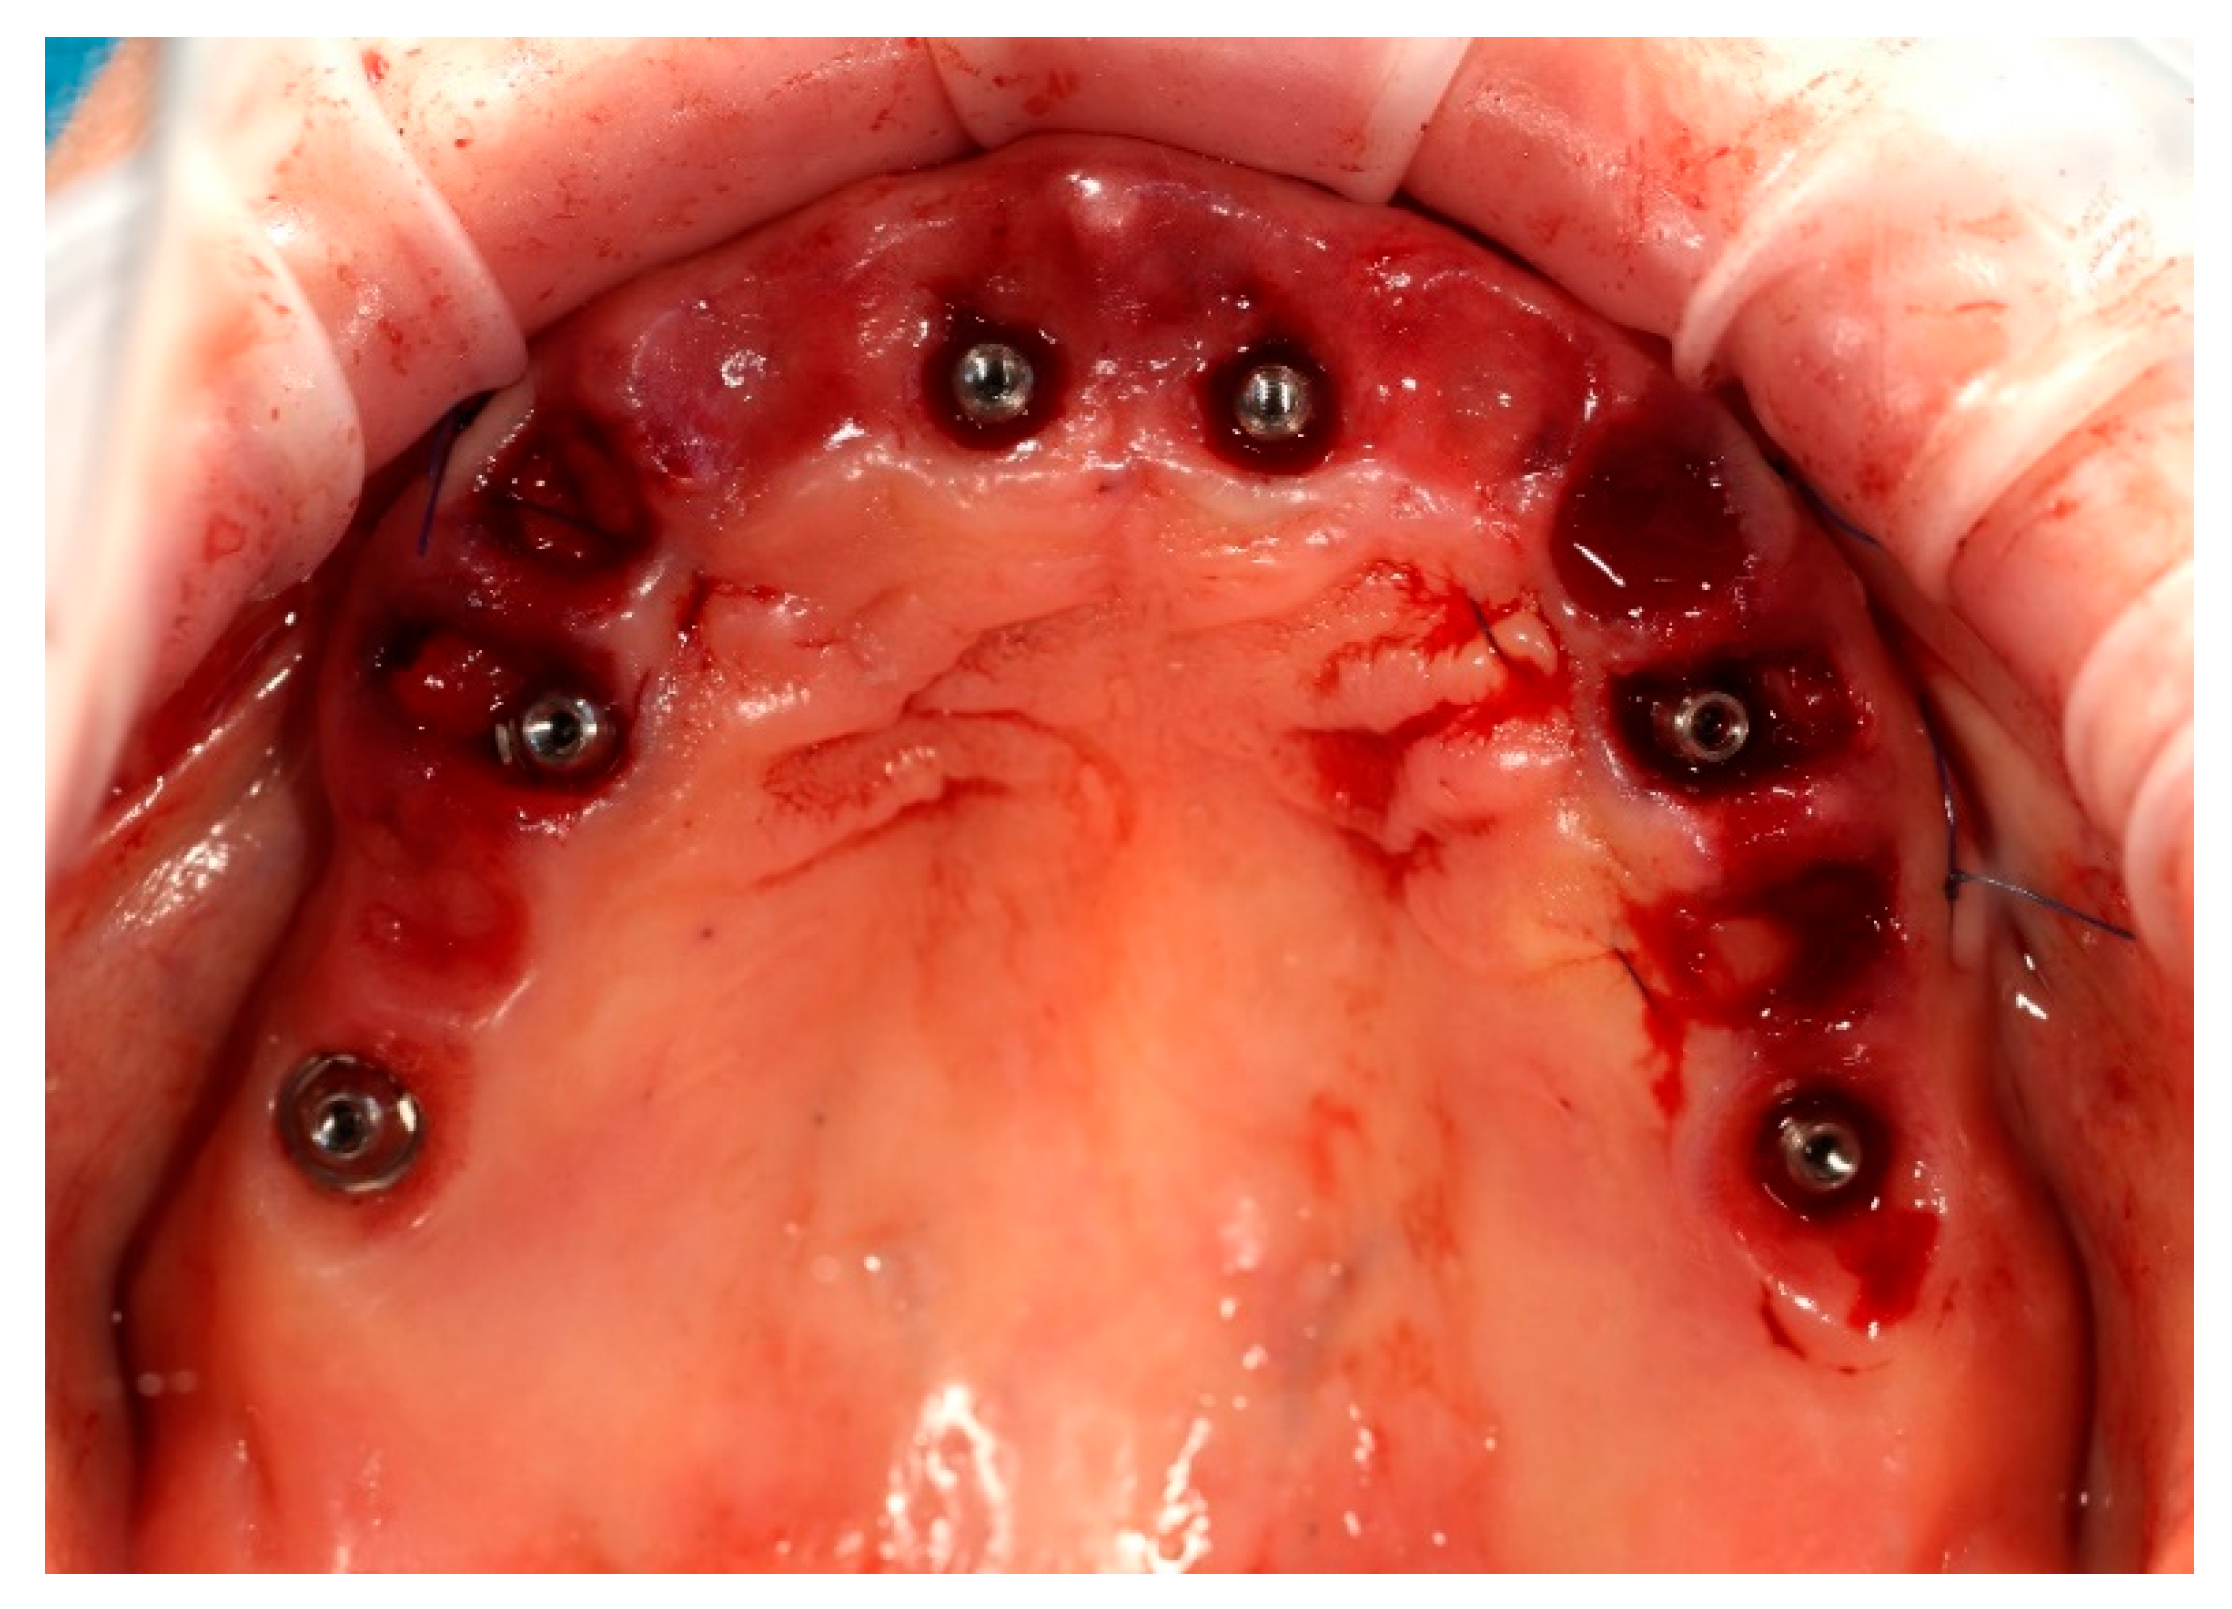

The surgical procedure was performed under local anaesthesia. In the first stage, teeth 13, 14, 23, 24, and 25 were atraumatically extracted. Immediately thereafter, two ICX Active implants (diameter 3.75 mm, length 12.5 mm) (ICX-Implant System; Medentis Medical GmbH, Bad Neuenahr-Ahrweiler, Germany) were inserted into the post-extraction sockets in positions 14 and 24. Excellent primary stability exceeding 35 Ncm was achieved for both implants. Two ICX Active implants were placed following the manufacturer’s drilling protocol, adapted to the clinical conditions of the post-extraction sockets (Figure 3).

Simultaneously, the existing implant-supported crowns in positions 16 and 26, as well as the anterior implant-supported bridge, were unscrewed from the supporting implants. Multi-unit abutments were then selected and secured onto all six supporting implants, including the newly placed implants at sites 14 and 24 (Figure 4).

Figure 4. Multi-unit abutments secured onto all six supporting implants, including the newly placed implants at positions 14 and 24, following removal of the existing restorations.